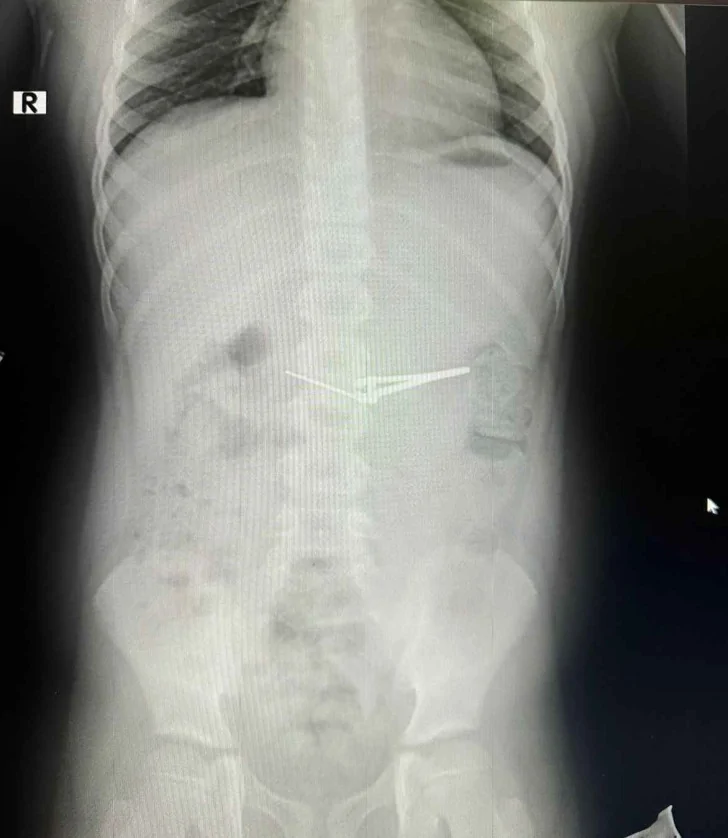

В Уфе врачи вытащили из желудка 6-летнего ребенка маникюрные ножницы

Медики из уфимской городской детской больницы №17 успешно извлекли из желудка шестилетнего мальчика щипцы для стрижки ногтей, об этом сообщили в пресс-службе Минздрава Башкирии. Для проведения процедуры извлечения была использована лечебная фиброгастроскопия под общим обезболиванием с применением специального устройства – эндокорзины.

Специалисты отметили, что благодаря точной работе устройства, удалось извлечь предмет без ущерба для слизистой оболочки желудка и пищевода. После успешного вмешательства состояние мальчика улучшилось, и через несколько дней ребенка выписали домой с соответствующими рекомендациями.